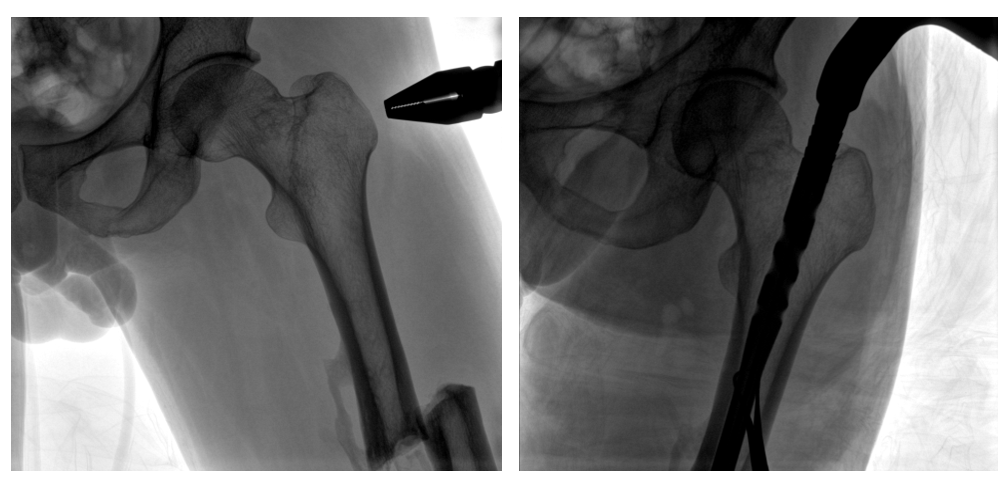

病例二:

患者左股骨干完全骨折,经过医生评估,使用“髓内钉内固定术”进行治疗。髓内钉内固定术需要将入钉点至骨折部位的影像完全展示,在一些长骨的骨折中,对视野范围要求高。

一体式C形臂钉点至骨折部位的临床影像

在进行髓内钉内固定术时,医生需要同时观察到入钉点和骨折部位的情况,PLX119C大平板一体式C形臂能够呈现更广阔的成像面积,满足大部分长骨髓内钉内固定术的摄片需求。